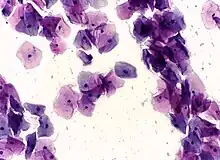

High-grade squamous intraepithelial lesion

In a typical scenario, about 0.5% of Pap results are high-grade SIL (HSIL), and less than 0.5% of results indicate cancer; 0.2 to 0.8% of results indicate Atypical Glandular Cells of Undetermined Significance (AGC-NOS).

• High-grade squamous intraepithelial lesion (HGSIL or HSIL)

Pap tests commonly examine epithelial abnormalities, such as metaplasia, dysplasia, or borderline changes, all of which may be indicative of CIN. Nuclei will stain dark blue, squamous cells will stain green and keratinised cells will stain pink/ orange. Koilocytes may be observed where there is some dyskaryosis (of epithelium). The nucleus in koilocytes is typically irregular, indicating possible cause for concern; requiring further confirmatory screens and tests.